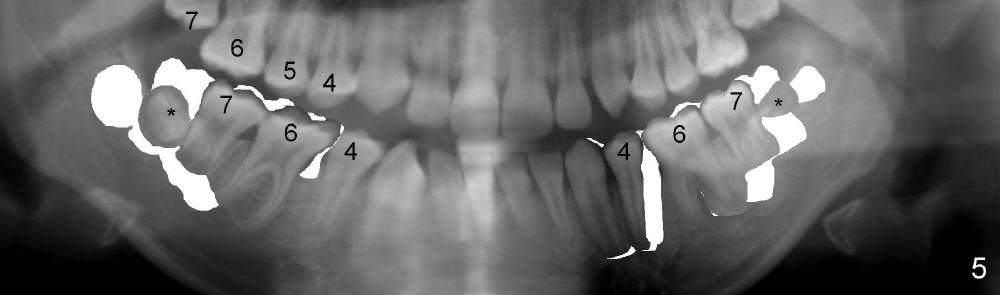

If RCT is successful for the lower left 1st molar, the lower right E is to be extracted.  All of the lower molars (including the third molars (Fig.5 *) will be moved mesially so that the final molar occlusion is Class III bilaterally.  This is Plan A.

Plan B is shown in Fig.6 when the LL 6 has to be removed due to RCT failure.  The orthodontic movement remains the same except LL6.  The edentulous space will be kept until the patient turns 18 years old.  An implant is placed (black box) and a crown is installed (red outline).